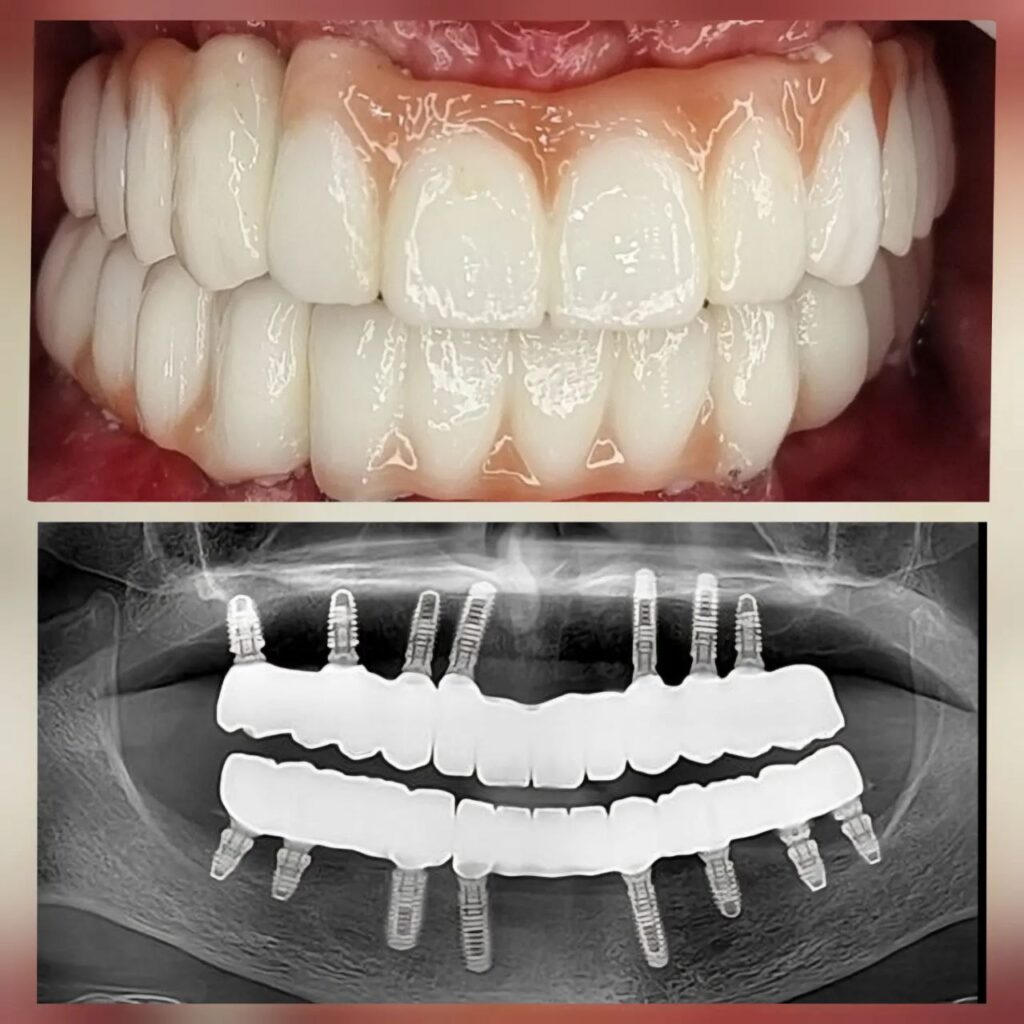

کاشت ایمپلنت دندان

اطمینان حاصل کردن از اینکه دندانهایتان به نحوی زیبا و طبیعی جایگزین شدهاند، از اهمیت بسیاری برخوردار است. ایمپلنت دندان به عنوان یک روش درمانی دائمی در دندانپزشکی شناخته میشود که حاصل آن، یک دندان زیبا و طبیعی در دهان شما خواهد بود.

هرچند که این روش درمانی هزینهی بیشتری نسبت به روشهای دیگر دارد، اما ارزش زیبایی که ایجاد میکند، قابل انکار نیست. ایمپلنتها به قدری شبیه به دندانهای طبیعی هستند که به سختی میتوان آنها را از دیگر دندانها تشخیص داد.